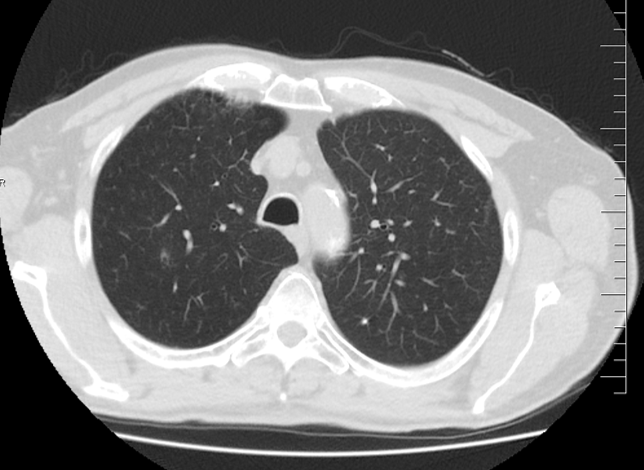

Pacient prošel multidisciplinární komisí, kde bylo onemocnění uzavřeno jak cT2 cN1 Mx s patologickou uzlinou v pánvi. Ale pro drobné plicní nodularity na bazích plic bylo doporučeno doplnit FDG PET/CT, které prokázalo patologické uzliny v pánvi a vícečetné plicní metastázy včetně ložiska v levém plicním hilu. Byla doplněna i bronchoskopie, která neprokázala bronchogenní tumor, bronchiální cytologie negativní.  V klinickém obraze se začínal rozvíjet mírný lymfedem obou dolních končetin. Dle prediktivního vyšetření TPS negativní, exprese PDL-1 méně než v 1% nádorových buněk, CPS pod 10. Celkově je pacient PS 1, občasné exacerbace CHOPN, dušnost při námaze, veden na plicní ambulanci.

Řez plicemi z CT screeningu: Stagingové PET/CT v 2/2021 potvrzuje plicní diseminaci.

Obr. 1Stagingové PET/CT v 2/2021 potvrzuje plicní diseminaci.